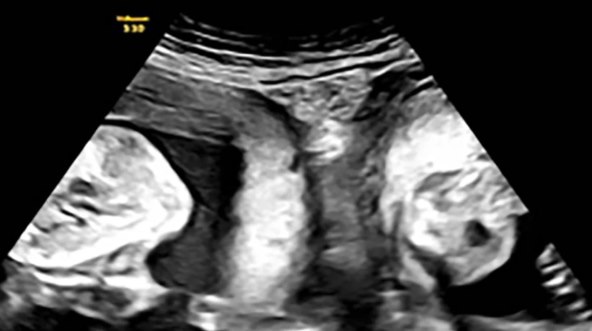

Čini se da je Liina priča pokazala sretan ishod nakon suočavanja s takvim okolnostima, a bolnica je otkrila da je prethodnu trudnoću izgubila. Ali u siječnju Li je ponovno zatrudnjela i otkrila je tijekom ranog ultrazvuka da ne očekuje samo jedno dijete već blizance - po jednog u svakoj maternici.

Nakon "pomnog i strogog" medicinskog nadzora, "uspješno" je rodila dječaka teškog 3,2 kg i djevojčicu tešku 2,4 kg, priopćila je bolnica.